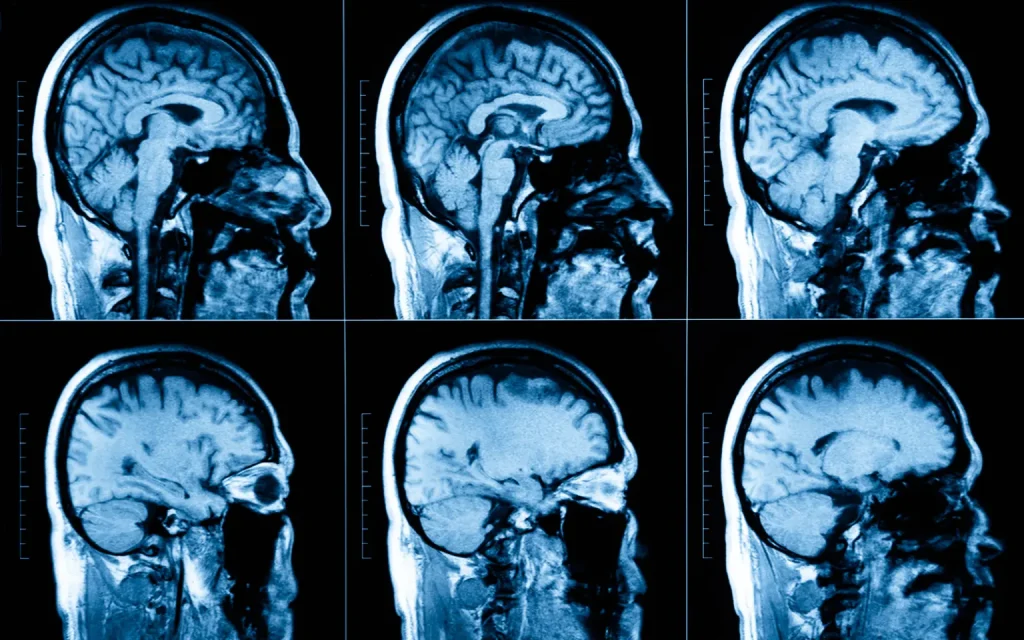

Maximum Resolution Imaging Center is equipped with the best MRI machine in Texas, i.e., the GE SIGNA Premier 3.0T MRI Scanner. Some of the significant features of this machine are as follows:

High Resolution Images